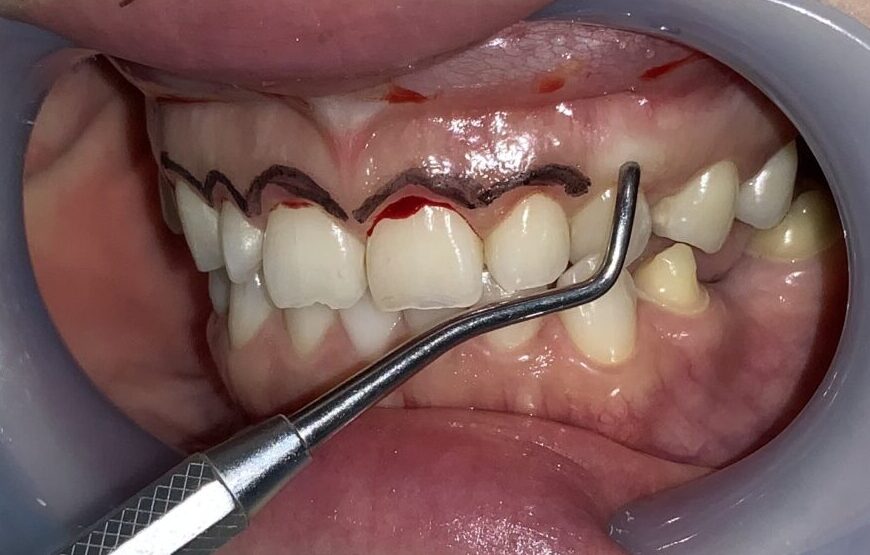

反対側の歯も同じように検査をしてみます。

歯に歯ぐきが大きくかぶっています。

歯ぐきを切り取る範囲を黒いマーキングペンでマーキングして、手術に挑みます。